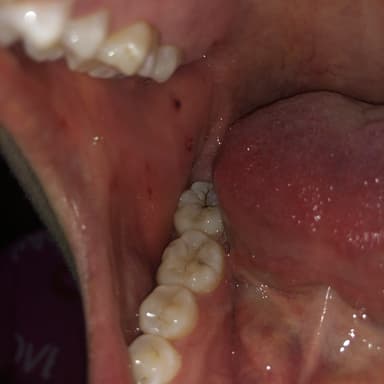

Bạch sản niêm mạc miệng là bệnh xuất hiện những mảng trắng hoặc xám trên lưỡi, phần mặt trên hay mặt dưới của lưỡi. Bệnh lý này thường không gây hại gì và có thể tự biến mất, nhưng nếu nghiêm trọng có thể dẫn đến những hệ lụy nghiêm trọng, đặc biệt là ung thư miệng.

– Vết loét có màu trắng và xám không thể rửa sạch được.

– Những mảng loét dày, cứng, phát triển trong khoảng từ vài tuần đến vài tháng.

– Không gây đau đớn, nhưng có thể nhạy cảm khi khi bệnh nhân ăn đồ cay nóng hay gặp các kích thích.